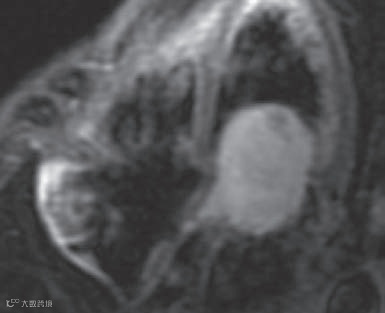

显示肿物边界清晰,有包膜,内部结构均匀,但未发现实性病变(图10和11)。以上检查均未显示肿瘤侵犯的证据,如房间隔不均匀或增厚,以及肿瘤向其他心腔延伸。

图10

图11